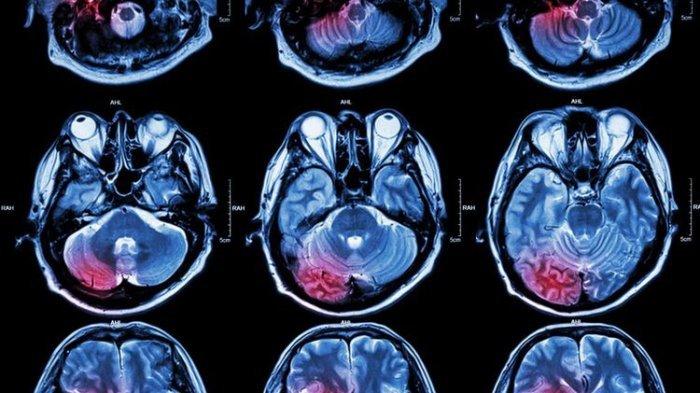

ilustrasi hasil MRI tumor otak

Ilustrasi hasil MRI otak

Ilustrasi hasil MRI otak (jateng.tribunnews.com)